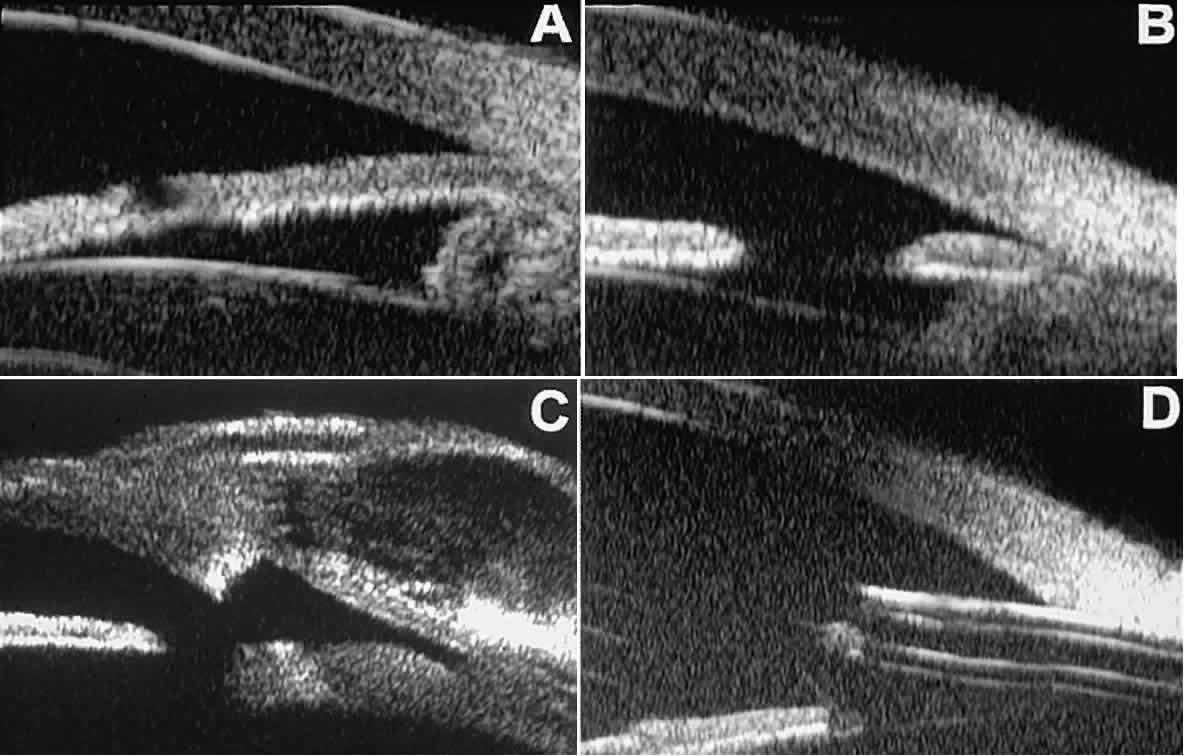

The role of UBM in the preoperative assessment of eyes with cataract is as yet unknown. In certain eyes, however, UBM may reveal features or abnormalities that could alter the ophthalmologist's surgical approach. Postoperatively, UBM can show the size and location of an intraocular lens (IOL) and the positioning of the haptics. A posterior chamber IOL appears on UBM as a highly reflective plate (corresponding to the lens optic) in the retropupillary plane with reverberation artifacts behind it (Fig. 17A). In contrast, an anterior chamber IOL appears on UBM as a sonoreflective plate located anterior to the pupillary plane (see Fig. 17B). In most eyes with a posterior chamber IOL, UBM can show whether the haptics are in the capsular bag (Fig. 18A), in the ciliary sulcus (see Fig. 18B), or in some other anatomic location12 (e.g., resting on the peripheral iris or secured with sutures to the sclera). The haptics are easier to locate if they are made of polymethyl-methacrylate than if they are made of proline because the former has a stronger reflectance.

Fig. 17. Composite UBM images of intraocular lenses. A. Posterior chamber IOL. B. Anterior chamber IOL.

Fig. 18 . Localization of posterior chamber IOL haptics by UBM. A. Haptic in capsular bag (arrow). B. Haptic (bright object just behind peripheral iris) in iridociliary sulcus.